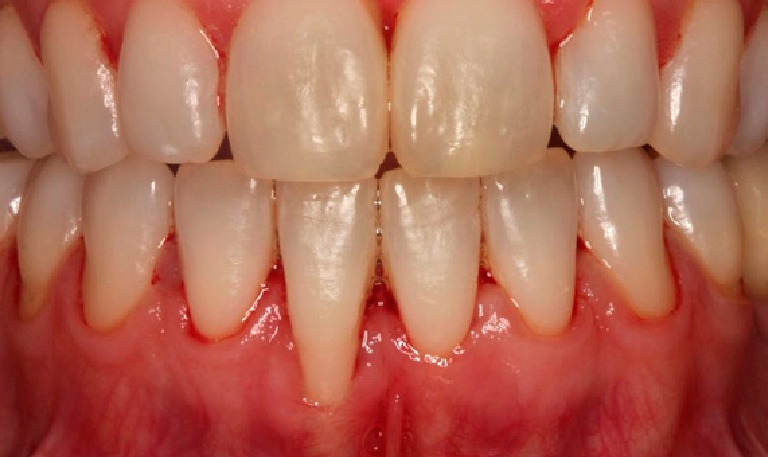

Blanqueamiento Dental

BeforeAfter